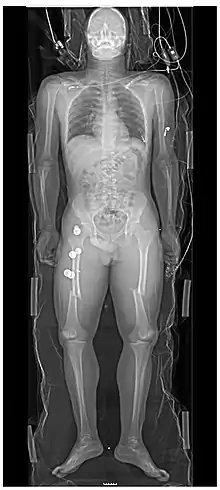

The standard abdominal X-ray protocol is usually a single anteroposterior projection in supine position.[15] A Kidneys, Ureters, and Bladder projection (KUB) is an anteroposterior abdominal projection that covers the levels of the urinary system, but does not necessarily include the diaphragm.